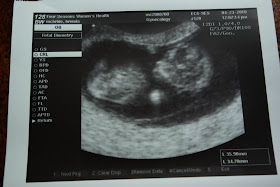

Today we went to the OBGYN to have our first sonogram of our precious little baby. Dr. Willis said everything looked "perfect." We took Noah and he was very well-behaved. Although by the time we had the ultrasound, he was pretty much unimpressed. That's o.k. Dr. Willis said that we're about a week ahead of where we thought we were.  We are officially 11 weeks & 3 days...almost done with the 1st trimester. Baby-On-The-Way is due November 9, 2010. Susie's first-born, Matthew has a birthday on November 9, and Denise's third, James, has a birthday of November 10th, so I'm thinking that every weekend in November is automatically booked by the time we celebrate these birthdays & have Thanksgiving!

Pregnancy Test, $20. Payment toward deductible, $50. Seeing our first picture of our Baby-On-The-Way...PRICELESS!